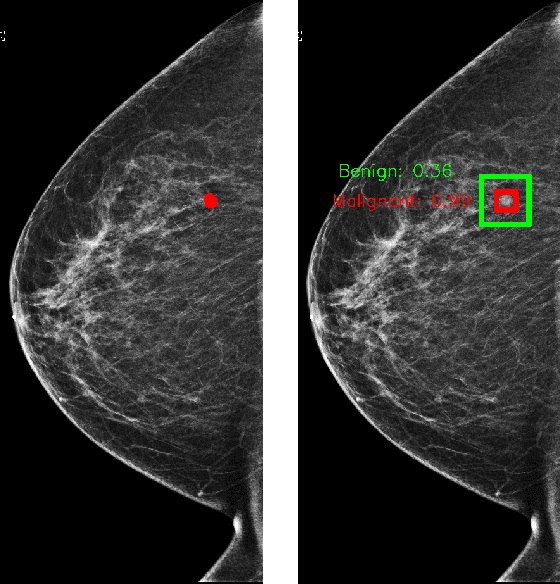

Abstract:We trained and evaluated a localization-based deep CNN for breast cancer screening exam classification on over 200,000 exams (over 1,000,000 images). Our model achieves an AUC of 0.919 in predicting malignancy in patients undergoing breast cancer screening, reducing the error rate of the baseline (Wu et al., 2019a) by 23%. In addition, the models generates bounding boxes for benign and malignant findings, providing interpretable predictions.

Abstract:We present a deep convolutional neural network for breast cancer screening exam classification, trained and evaluated on over 200,000 exams (over 1,000,000 images). Our network achieves an AUC of 0.895 in predicting whether there is a cancer in the breast, when tested on the screening population. We attribute the high accuracy of our model to a two-stage training procedure, which allows us to use a very high-capacity patch-level network to learn from pixel-level labels alongside a network learning from macroscopic breast-level labels. To validate our model, we conducted a reader study with 14 readers, each reading 720 screening mammogram exams, and find our model to be as accurate as experienced radiologists when presented with the same data. Finally, we show that a hybrid model, averaging probability of malignancy predicted by a radiologist with a prediction of our neural network, is more accurate than either of the two separately. To better understand our results, we conduct a thorough analysis of our network's performance on different subpopulations of the screening population, model design, training procedure, errors, and properties of its internal representations.